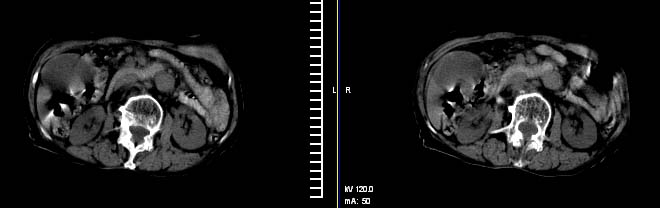

以下是引用有风的日子在2008-3-28 16:21:00的发言:[br]肝内胆管略扩张、胆囊明显增大、张力增高,肝门及胰头部软组织团块影、分界欠清晰,腰椎增生并骨质疏松。考虑占位病变,建议肝门及胰头部增强薄扫,以进一步明确诊断。

以下是引用拾荒者在2008-3-28 22:10:00的发言:[br]胆囊增大,张力较高,周围尚清晰,环绕十二指肠降段低密度影,考虑1.慢性胆囊炎,2环状胰腺?胰头占位?建议增强扫描!